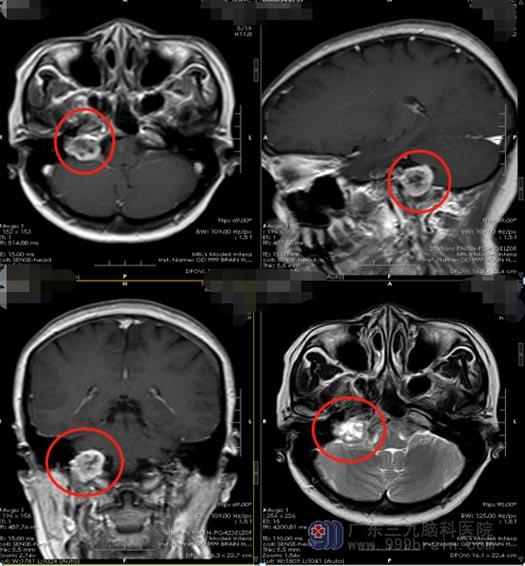

林大姐自去年2月份出现声音嘶哑,当地医院考虑是声带麻痹,予以手术治疗。3个前,她开始有咳嗽、吞咽困难、右侧耳鸣等症状,头颅MR检查提示:右侧颈静脉孔区占位性病变,考虑神经鞘瘤。

颈静脉孔区肿瘤一经确诊,一般采取手术治疗,手术目的是尽可能一期完全切除,同时尽可能保护神经功能。因其位置深在,生长方式多样,解剖关系复杂,与后组颅神经、脑干、颈内动静脉等关系密切,手术难度大,颅内外沟通型神经稍瘤的手术难度就更大,对后组颅神经、面听神经、脑干、椎基底动脉、颈内静脉、乙状窦的术中保护是手术的难点和重点。

入住广东三九脑科医院后,医院副院长、神经外五科主任鲁明带领团队对林大姐的病情进行了仔细的讨论,完善相关检查后,由鲁明主刀在全麻下行“右侧颈静脉孔区颅内外沟通神经鞘瘤切除术”,显微镜下全切直径约3cm的肿瘤,术中面、听、三叉神经保留完好。术后林大姐无咳嗽,吞咽困难症状得到改善,已顺利康复出院。